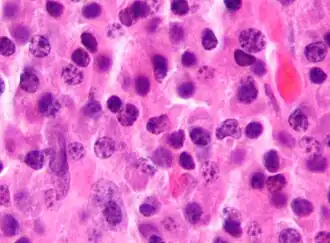

Миеломная болезнь (от др.-греч. μυελός — костный мозг и -ωμα — окончание в названиях опухолей, от ὄγκωμα — опухоль), множественная миелома, генерализованная плазмоцитома или болезнь Рустицкого-Калера — злокачественная опухоль из плазматических клеток (дифференцированных B-лимфоцитов, продуцирующих антитела). Заболевание системы крови, относящееся к парапротеинемическим лейкозам. Своё название заболевание и опухолевая клетка получили в связи с преимущественной локализацией процесса в костном мозге.

Опухолевая ткань разрастается преимущественно в плоских костях (череп, рёбра, таз) и в позвоночнике, инициируя в них остеолизис[6] и остеопороз. На рентгенограмме очаги поражения имеют вид гладкостенных пробоин. Полости образуются в местах роста миеломных клеток за счёт активации ими остеокластов, осуществляющих лизис и резорбцию костной ткани («пазушное» рассасывание). Помимо костного мозга, опухолевые инфильтраты могут обнаруживаться и в других органах.